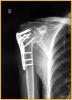

锁定板治疗老年人骨质疏松性移位的肱骨近端骨折

患者女,72岁,诊断为:肱骨近端骨折。

行肱骨近端锁定型钉板(PHILOS)固定术,手术过程:采用全麻或斜方肌阻滞麻醉,用沙滩椅体位,术中肱骨头复位后,用二至三枚克氏针临时固定保持复位,并使其余骨折块复位,然后透视确认复位质量。用5号不可吸收缝线将大小结节缝合修复,再选用适当长度的锁定钉板置于肱骨近端和肱骨干的外侧面。注意避免将钢板放置的过高以致成角螺钉的位置不合适而不能达到最佳骨接触。可用一枚非锁定螺钉固定于肱骨干上可使钢板远近端滑动调整位置。然后使用导向器上锁定螺钉使钢板和螺钉一体化。固定完成后再次透视确认无误,处理好软组织后逐层关闭切口。